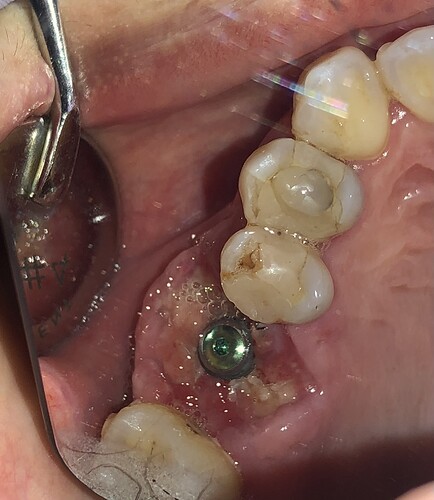

Did an immediate implant placement on tooth 26 with bone graft and cover with d-PTFE membrane (Permamem). 5 days later noted the sutures were loose but the membrane still in position. I re-fix the membrane. One week later, the membrane was partially dislodged. No sign of infection and there were epithelial growth under the membrane. I removed the membrane, irrigate with CHX copiously and instruct the patient to irrigate daily. But I noticed implant thread exposure at the crestal level. Will it help if I leave it be as long as there are no infection, and do a connective tissue graft when I place the healing abutment?

As long as the implant has good primary stability i would leave it alone. the tissues will re-epithelialize and will heal like a normal socket. U can also change the cover screw to a wide healing collar for a transmucosal healing. next time plan to place the implant a couple of mm subcrestal when doing an immediate.JC comments: